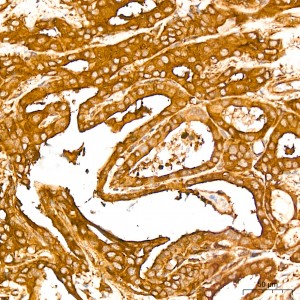

| Immunohistochemistry analysis of paraffin-embedded Human thyroid cancer tissue using NF-kB p65/RelA Rabbit mAb (A19653) at a dilution of 1:800 (40x lens). High pressure antigen retrieval performed with 0.01M Citrate Bufferr (pH 6.0) prior to IHC staining. |

| Immunohistochemistry analysis of paraffin-embedded Human tonsil tissue using NF-kB p65/RelA Rabbit mAb (A19653) at a dilution of 1:800 (40x lens). High pressure antigen retrieval performed with 0.01M Citrate Bufferr (pH 6.0) prior to IHC staining. |

| Immunohistochemistry analysis of paraffin-embedded Mouse spleen tissue using NF-kB p65/RelA Rabbit mAb (A19653) at a dilution of 1:800 (40x lens). High pressure antigen retrieval performed with 0.01M Citrate Bufferr (pH 6.0) prior to IHC staining. |

| Immunohistochemistry analysis of paraffin-embedded Rat spleen tissue using NF-kB p65/RelA Rabbit mAb (A19653) at a dilution of 1:800 (40x lens). High pressure antigen retrieval performed with 0.01M Citrate Bufferr (pH 6.0) prior to IHC staining. |